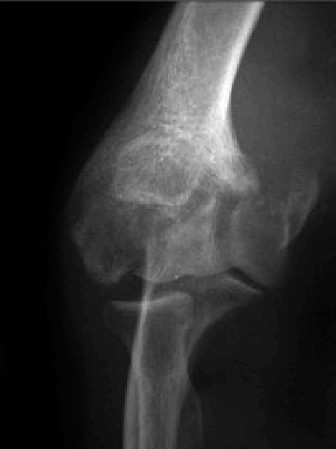

Treat a patient with infected total shoulder arthroplasty? CASE 21 A 70-year-old, right-hand-dominant female presents to clinic complaining of 4 years of gradually worsening chronic right shoulder pain and stiffness. She says the pain is worse at night and with any range of motion, denies a history of trauma, pain in other extremities, or numbness or tingling of the right upper extremity. She notes that her mother suffered from rheumatoid arthritis that affected her shoulder. Physical examination reveals decreased muscle bulk over the right supra- and infraspinatus fossae compared to the contralateral side, limited active and passive ROM, marked weakness with external rotation, and 4+/5 strength with shoulder abduction. X-rays of the right shoulder are shown in Figures 2–58 and 2–59.

Figure 2–58

Figure 2–59

The correct answer is (C). Rotator cuff tear arthropathy consists of a combination of rotator cuff insufficiency, glenohumeral joint degenerative changes, and superior humeral head migration. It is more common in women and also more often found on the dominant side. The patient’s clinical examination with weakened external

rotation and muscle atrophy signaling incompetent supra- and infraspinatus muscles point to rotator cuff insufficiency, and her plain films reveal narrowed glenohumeral joint space as well as superior migration of the humeral head. Choice D is incorrect because, while radiographs would show narrowing of the glenohumeral joint space, they would also likely show numerous osteophytes and posterior wear of the glenoid. Choice B is incorrect because, while adhesive capsulitis does present as decreased active and passive range of motion, the patient’s constellation of symptoms pointing towards rotator cuff insufficiency along with the radiographs make cuff tear arthropathy the more likely choice. Finally, Choice A is incorrect because even though she has a positive family history of rheumatoid arthritis, it is less likely to present only in a single joint. Also, rheumatoid arthritis on radiography appears more as an erosive process without the characteristic superior migration of the humeral head.